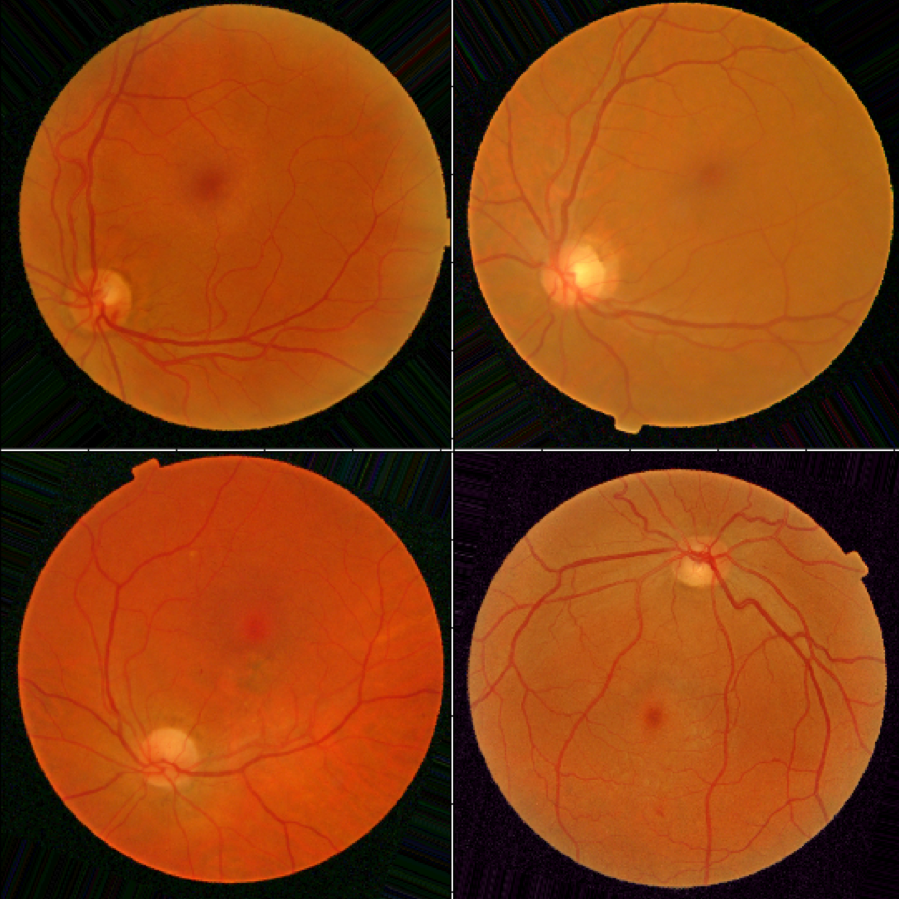

4.2 Dataset

The Messidor dataset [15] is a collection of eye fundus images of healthy and unhealthy patients. It consists of eye fundus color numerical images acquired by 3 ophthalmologic departments. The image sizes are , or pixels. The retinopathy grade has been provided by medical experts, where a grade of 0 corresponds to healthy and grades 1,2 and 3 correspond to unhealthy.

The training data consists of 949 images, 441 healthy and 508 unhealthy, and the test data consists of 238 images, 106 healthy and 132 unhealthy. The images in both training an test set are distributed equally among the 3 opthalmologic departments.